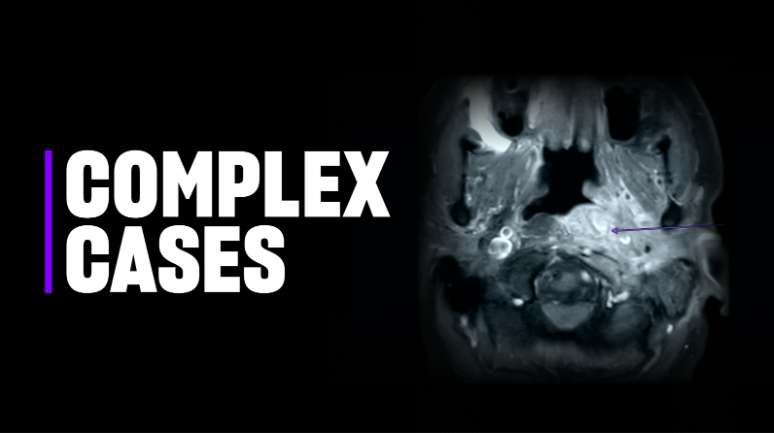

Dr. Riina initially performed diagnostic and rotational angiography with 3D reconstructions (Slide 1) to better characterize the vascular pathology and to inform clinical decision-making. The detailed imaging confirmed the exact size and location of the AVM, as well as the arterial branches feeding it. The imaging also revealed several areas of the lesion featuring a high risk for potential bleeding.

Functional MRI (fMRI) with diffusion tractography, conducted by neuroradiologist Timothy M. Shepherd, MD, PhD, confirmed that the AVM did not involve eloquent cortical regions and provided detailed mapping of the patient’s white matter anatomy (Slide 2).

“Dr. Riina and I determine eloquence based on direct fMRI visualization of patient tasks,” Dr. Shepherd says. “We also look at additional important cortical regions, like frontal eye fields and the supplementary motor area. We then map the white matter anatomy that connects all these regions.” This advanced imaging provides a more complete picture for safer treatment planning, Dr. Shepherd says.